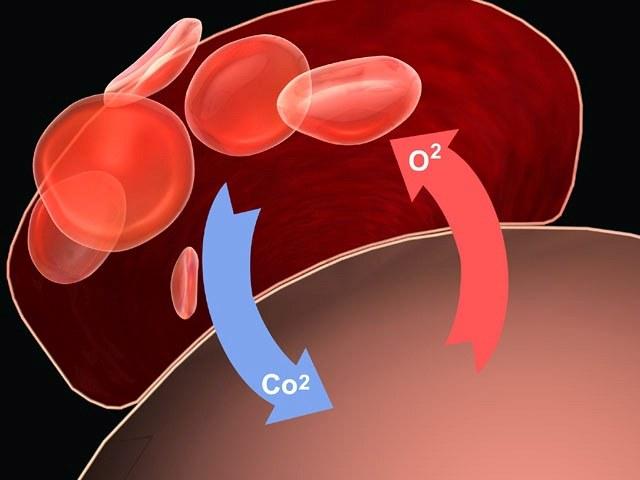

Врачи единодушно подчеркивают, что курение оказывает разрушительное воздействие на легкие, приводя к структурным и физиологическим изменениям. При регулярном вдыхании табачного дыма происходит повреждение альвеол, что нарушает газообмен и снижает уровень кислорода в крови. Со временем это может привести к хроническим заболеваниям, таким как хроническая обструктивная болезнь легких (ХОБЛ) и эмфизема. Врачи отмечают, что курение также способствует воспалению дыхательных путей, увеличивая риск инфекций и обострений астмы. Кроме того, наблюдается утолщение стенок бронхов и образование слизи, что затрудняет дыхание. В результате, пациенты, продолжающие курить, сталкиваются с ухудшением качества жизни и значительными рисками для здоровья.

Так как легкие при курении сжимаются, их вентиляционная функция нарушается, газообмен осуществляется в неполном объеме. Это приводит к развитию гипоксии (кислородное голодание) всех органов и систем. Человек испытывает чувство нехватки воздуха.

Гипоксия приводит к тяжелым последствиям – поражение мозга и нервной системы с развитием судорог, умственной дисфункцией, комой. При гипоксии возрастает риск асфиксии (удушья) во время сна.

При попадании яда в легкие возникает нарушение кровообращения. Развивается легочная гипертензия, повышается давление в легочной артерии. С разрушение артериол капиллярное русло становится пустым, а в кровеносных сосудах развивается атеросклероз. Это усиливает работу сердца и гипертрофирует миокард.